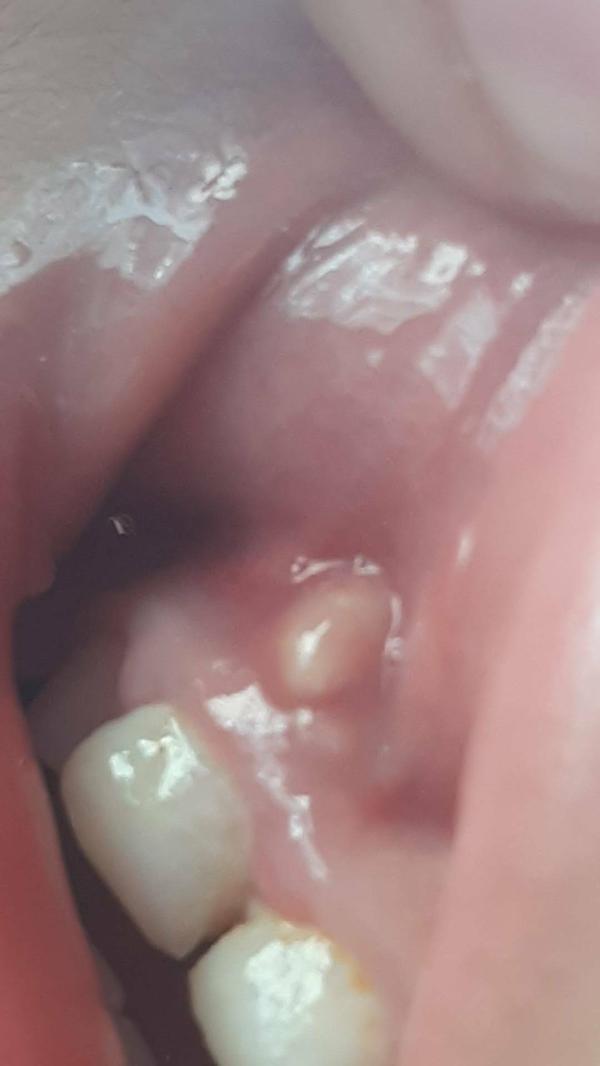

Девочки что этл может быть ребенку 2 годика

Эпулис возможно, нужно к челюстно-лицевому хирургу обратиться

На кисту похоже